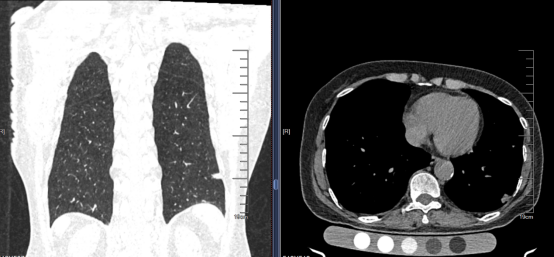

在进行了胸部CT扫描后,张挪富教授发现她的“左肺下叶外基底段有一个大约10×10mm的实性结节,结节呈现出浅分叶状,其性质尚未确定,肿瘤的可能性尚未排除”。

他们发现,通过超声虽然可以显示出该病灶,但该病灶可显示的范围较小(大小约8mm×7mm),随呼吸若隐若现,通过多切面观察及评估,在患者呼吸配合下终于找到一条安全的穿刺路径,但需要操作时精准定位及配合,否则很容易出现局部气胸及取材不足。通过超声定位病灶。局部进行麻醉,在超声引导下,避开大血管和重要脏器,仅靠针孔大小的伤口,就可以精准地在病灶处穿刺取材。